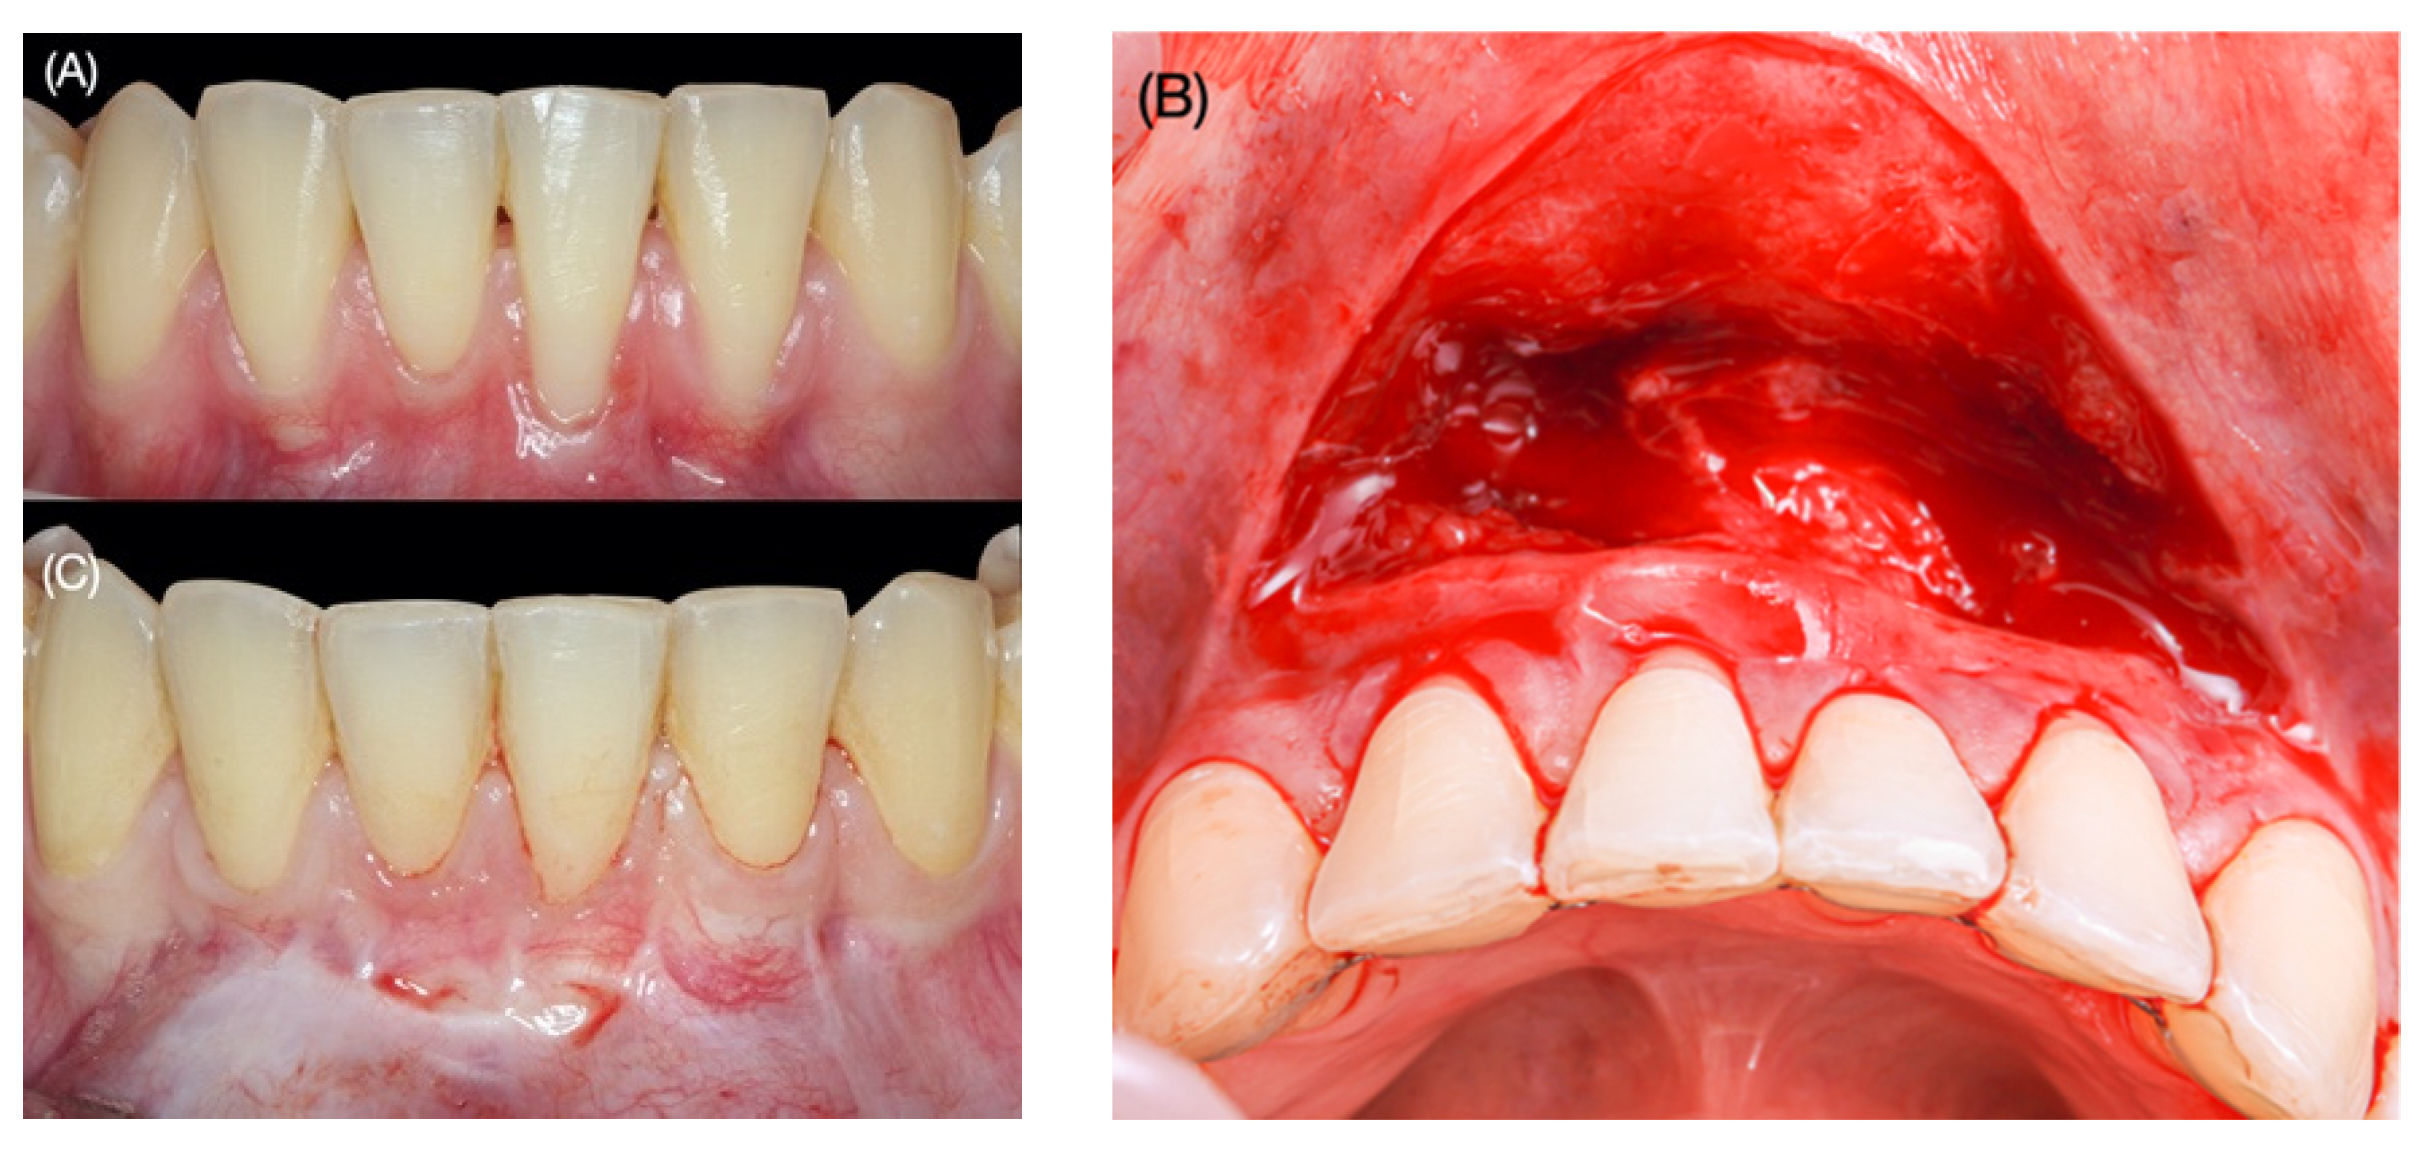

Clinical Outcomes of the Double Lateral Sliding Bridge Flap Technique with Simultaneous Connective Tissue Graft in Sextant V Recessions: Three-Year Follow-Up Study

2.1. Surgical Protocol